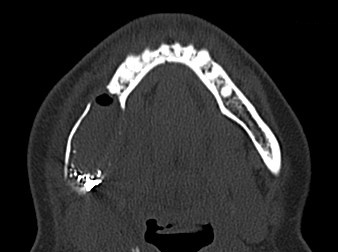

Ein ergänzend durchgeführtes Denta-CT des Unterkiefers (Abbildungen 2 und 3) zeigte eine zystische Raumforderung im Bereich der rechten Unterkieferhälfte, welche bis weit in den aufsteigenden rechten Unterkieferast reichte. Der Nervkanal des rechten N. mandibularis verlief durch die Raumforderung und ließ sich nicht sicher abgrenzen.